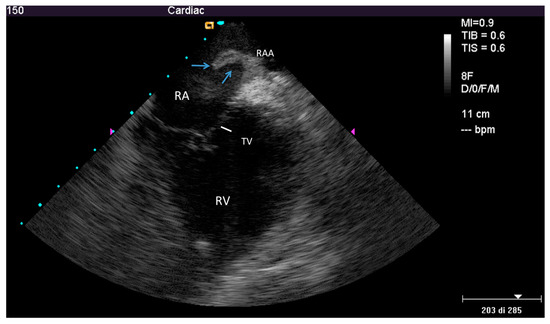

2.2.2. After the Extraction

3.2. Post-extraction ICE